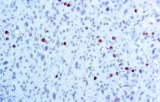

Gli anticorpi primari contro il recettore degli estrogeni (ER), recettore del progesterone (PR), HER2 e Ki-67 rimangono il pilastro della classificazione e delle decisioni terapeutiche nel cancro al seno. Questi anticorpi sono validati clinicamente e marcati CE/IVD per garantire una rilevazione affidabile e riproducibile dei biomarcatori – cruciale per guidare la terapia ormonale e le strategie di trattamento mirato.